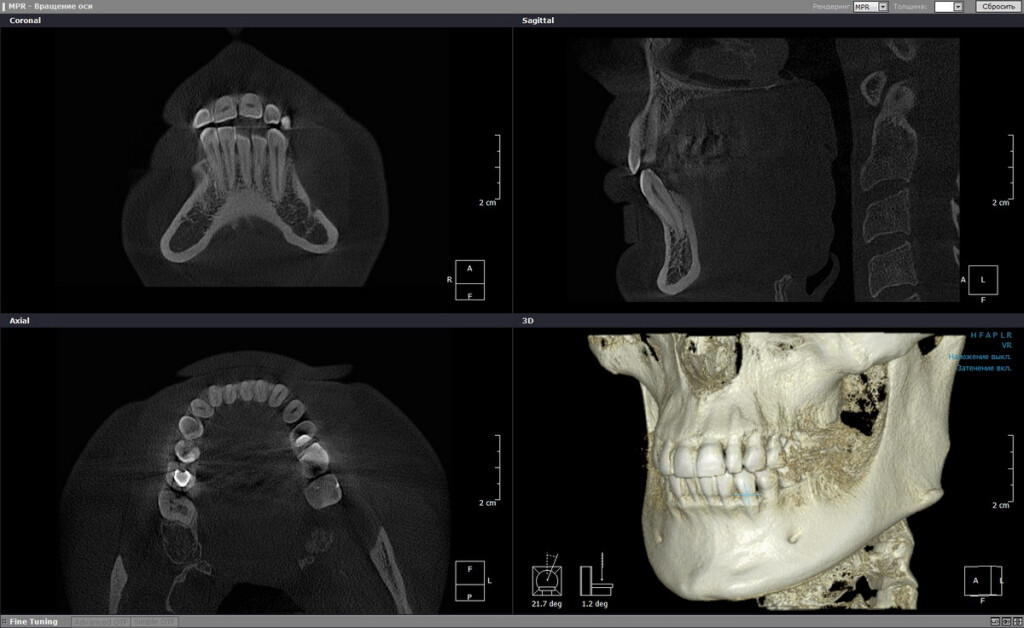

Медицина

Каждый воксель содержит информацию не только о местоположении, но и о плотности ткани (для КТ) или о типе сигнала (для МРТ). Это позволяет врачу не просто увидеть орган, а анализировать его структуру, находить патологии, точно планировать операции и проводить виртуальные исследования.